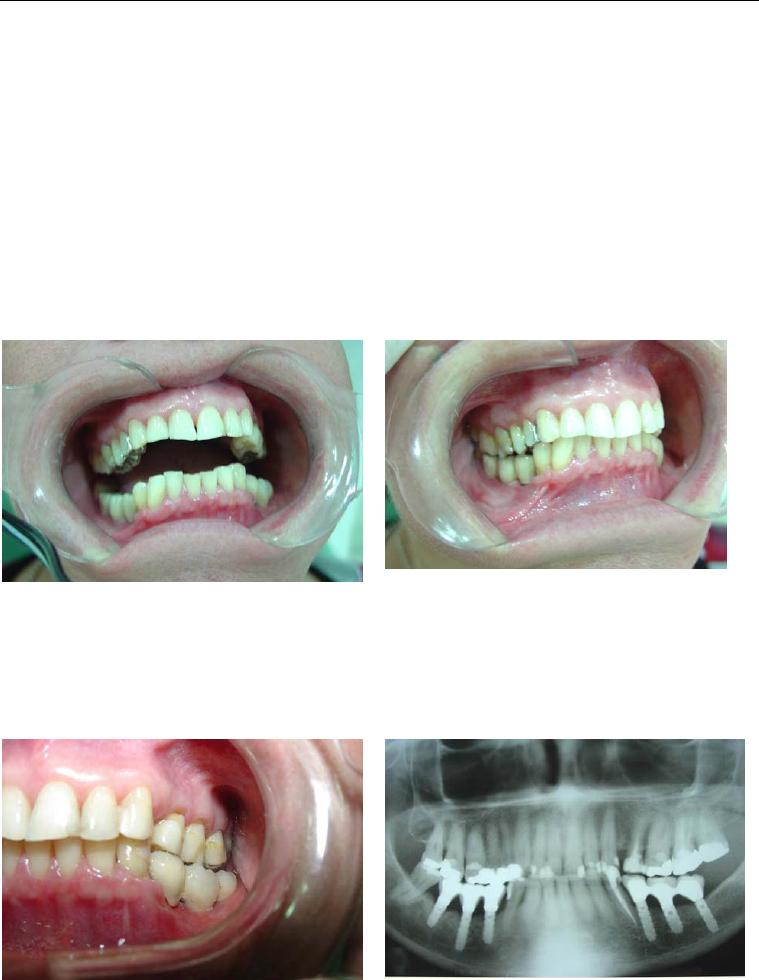

Foi no intuito de transpor estas dificuldades que se idealizou o sistema de

implante inicialmente conhecido como Wedge (figura 1) e que, após dez anos de